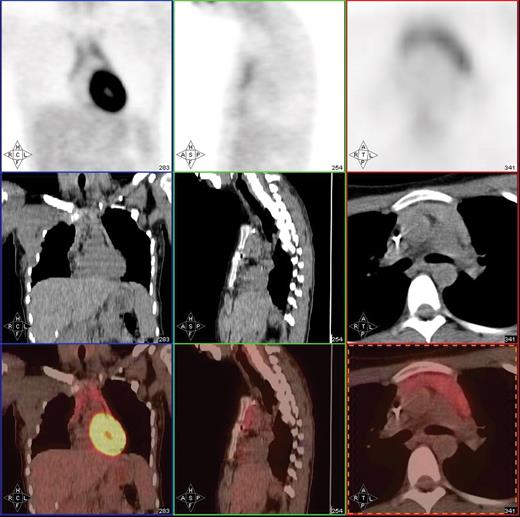

Post-treatment PET/CT scan in a 20-year-old patient with Hodgkin lymphoma showing thymic hyperplasia with otherwise no PET evidence of disease.